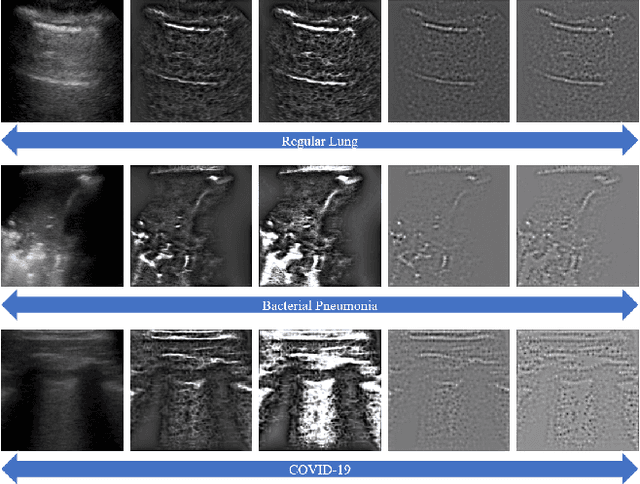

The global pandemic of the novel coronavirus disease 2019 (COVID-19) has put tremendous pressure on the medical system. Imaging plays a complementary role in the management of patients with COVID-19. Computed tomography (CT) and chest X-ray (CXR) are the two dominant screening tools. However, difficulty in eliminating the risk of disease transmission, radiation exposure and not being costeffective are some of the challenges for CT and CXR imaging. This fact induces the implementation of lung ultrasound (LUS) for evaluating COVID-19 due to its practical advantages of noninvasiveness, repeatability, and sensitive bedside property. In this paper, we utilize a deep learning model to perform the classification of COVID-19 from LUS data, which could produce objective diagnostic information for clinicians. Specifically, all LUS images are processed to obtain their corresponding local phase filtered images and radial symmetry transformed images before fed into the multi-scale residual convolutional neural network (CNN). Secondly, image combination as the input of the network is used to explore rich and reliable features. Feature fusion strategy at different levels is adopted to investigate the relationship between the depth of feature aggregation and the classification accuracy. Our proposed method is evaluated on the point-of-care US (POCUS) dataset together with the Italian COVID-19 Lung US database (ICLUS-DB) and shows promising performance for COVID-19 prediction.